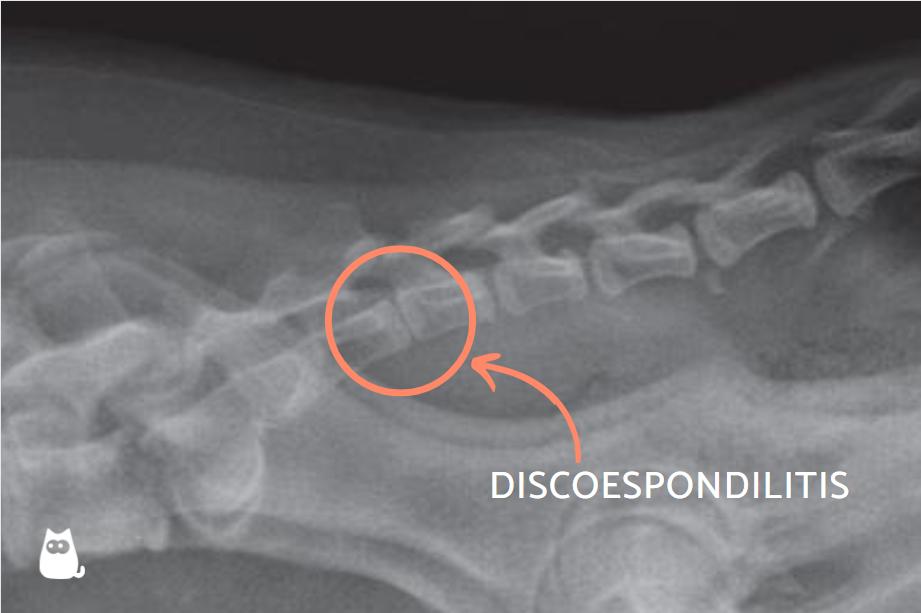

Los cambios que aparecen en la radiografía de la discoespondilitis canina consisten en colapso del espacio discal, erosión de la lámina terminal y lisis focal de una o de las dos láminas terminales vertebrales. Son también visibles cambios proliferativos en los huesos adyacentes al espacio discal y esclerosis en los márgenes de la pérdida de hueso. Como es frecuente que esta enfermedad no solo se asiente en un espacio discal, se deben realizar placas radiográficas de toda la columna del perro.